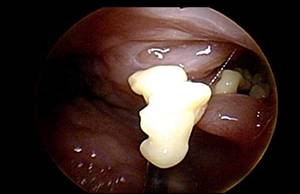

편도결석은 편도 혹은 편도선에 있는 작은 구멍에 음식물 찌꺼기와 세균이 뭉쳐서 생기는 작고 노란 알갱이다. 편도에는 편도음와라는 작고 깊은 구멍이 있는데, 그곳에 음식의 잔여물과 세균이 뭉쳐있으면 악취가 나게 된다. 결석이라고 해서 신체 다른 부위의 결석처럼 딱딱한 것은 아니고, 크기 또한 매우 작다. 편도결석이 있으면 평소 양치질을 열심히 하고, 치아와 혀의 상태가 깨끗한데도 입 냄새가 나기 쉽다. 목이 아프거나 뭔가 걸린 것 같은 이물감이 들고, 무언가 삼킬 때 불편함을 느낄 수도 있다. 입을 크게 벌리면 편도 안쪽에 있는 결석이 보일 때도 있지만, 대부분 깊숙이 박혀있어 보이지 않다가 양치질이나 기침, 구역질을 할 때 튀어나온다.